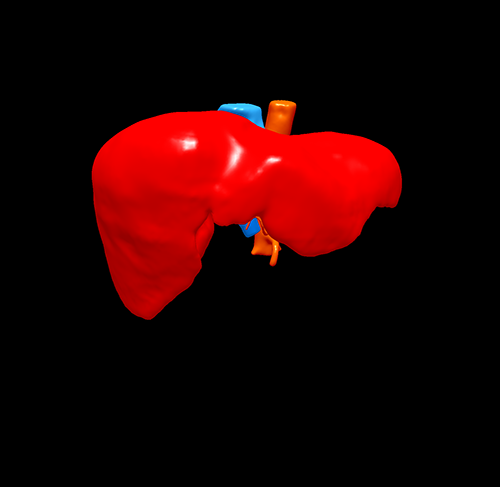

S8肝癌---改良肝中叶切除(3D打印)